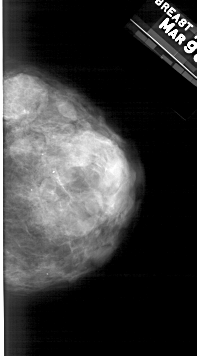

A_1484_1.RIGHT_MLO

RIGHT_MLO LINES 5461 PIXELS_PER_LINE 2866 BITS_PER_PIXEL 12 RESOLUTION 43.5 NON_OVERLAY